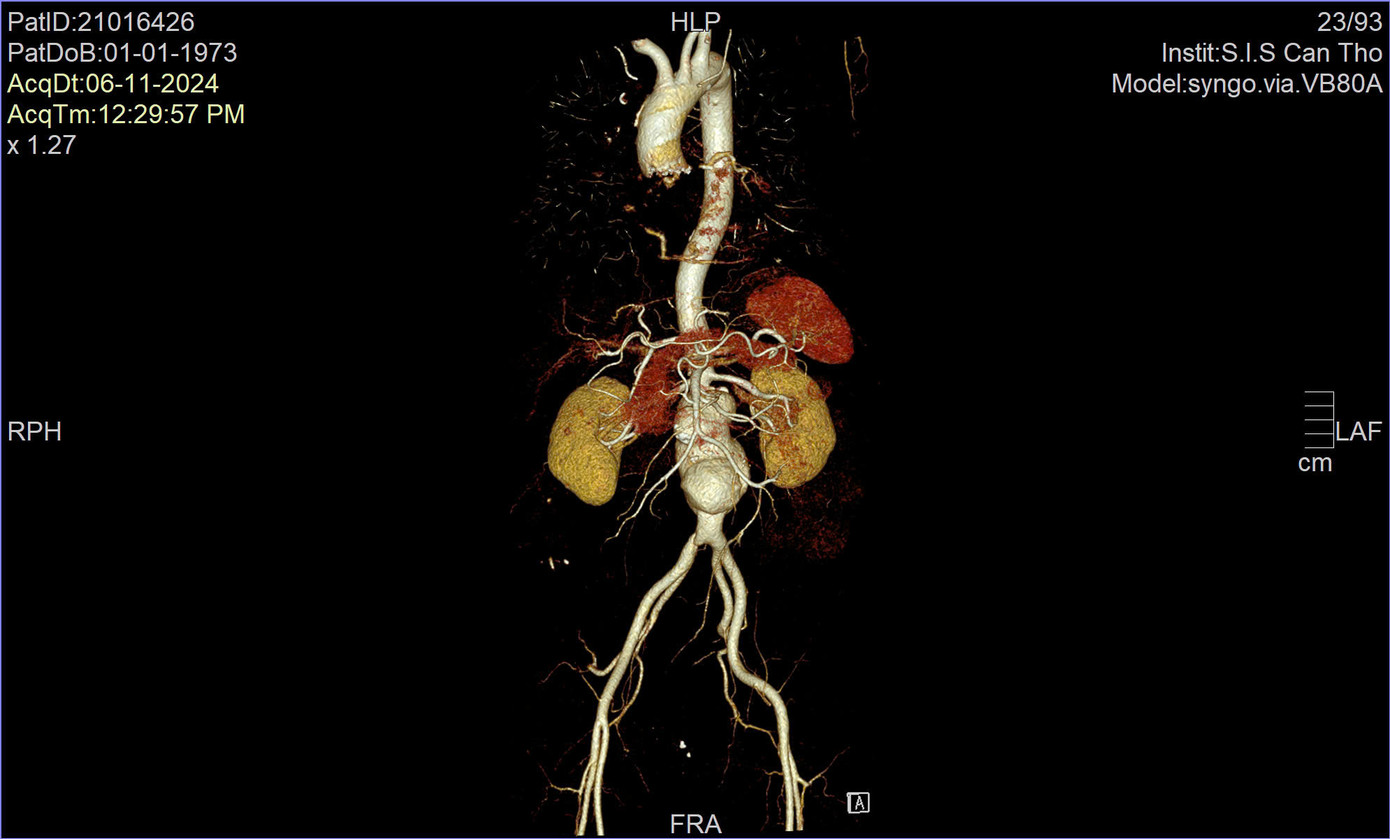

| Động mạch chủ bụng của bệnh nhân bị phình lớn dọa vỡ, đe dọa tính mạng |

Lo lắng trước biểu hiện bất thường, gia đình đưa người bệnh đến Bệnh viện S.I.S Cần Thơ. Qua siêu âm, các bác sĩ nghi ngờ bệnh nhân bị phình động mạch chủ bụng đoạn dưới thận. Để chẩn đoán chính xác hơn, các bác sĩ chỉ định chụp CT scan ổ bụng. Kết quả ghi nhận phình động mạch chủ bụng dưới thận, dọa vỡ, với kích thước khổng lồ (ngang 70; trước sau 90; dài 131mm) kéo dài đến vị trí chia đôi động mạch chậu.